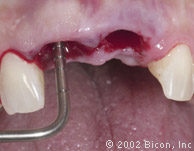

Вид спустя десять недель после установки имплантантов

Установка двух 3.0mm Impression Post

Снятие слепка и подбор цвета

Произведены послабляющие разрезы